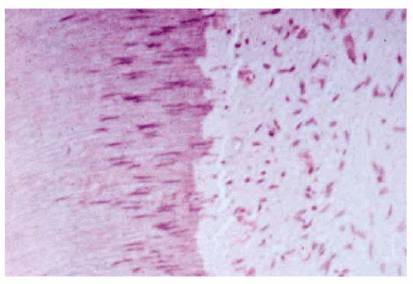

Following caries, the single most influencing factor on the health of the pulp

(Figure 19-26) is the operator. Simply modifying

traumatic operative techniques could easily prevent sequelae and reduce the

eventual need for iatrogenically required endodontics.

Figure 19-26: A vital healthy pulp with a typical pattern of palisading odontoblasts. (Photograph courtesy of Dr. Harold R. Stanley.)

Regardless of the source, the odontoblasts will react. It is only a question of